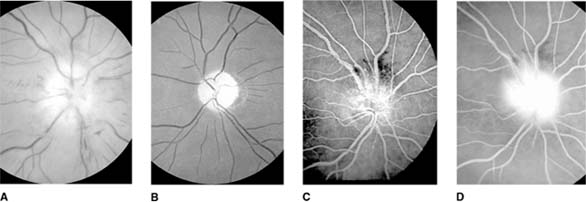

Figure 14-15

Figure 14-15: Chronic papilledema with prominent disk swelling, capillary dilation, and retinal folds but few hemorrhages or cotton-wool spots (A) and (B). Fluorescein angiography demonstrates the capillary dilation in its early phase (C) and marked disk leakage in its late phase (D).